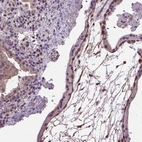

Immunohistochemical staining of human placenta shows moderate membranous/cytoplasmic positivity in trophoblastic cells.